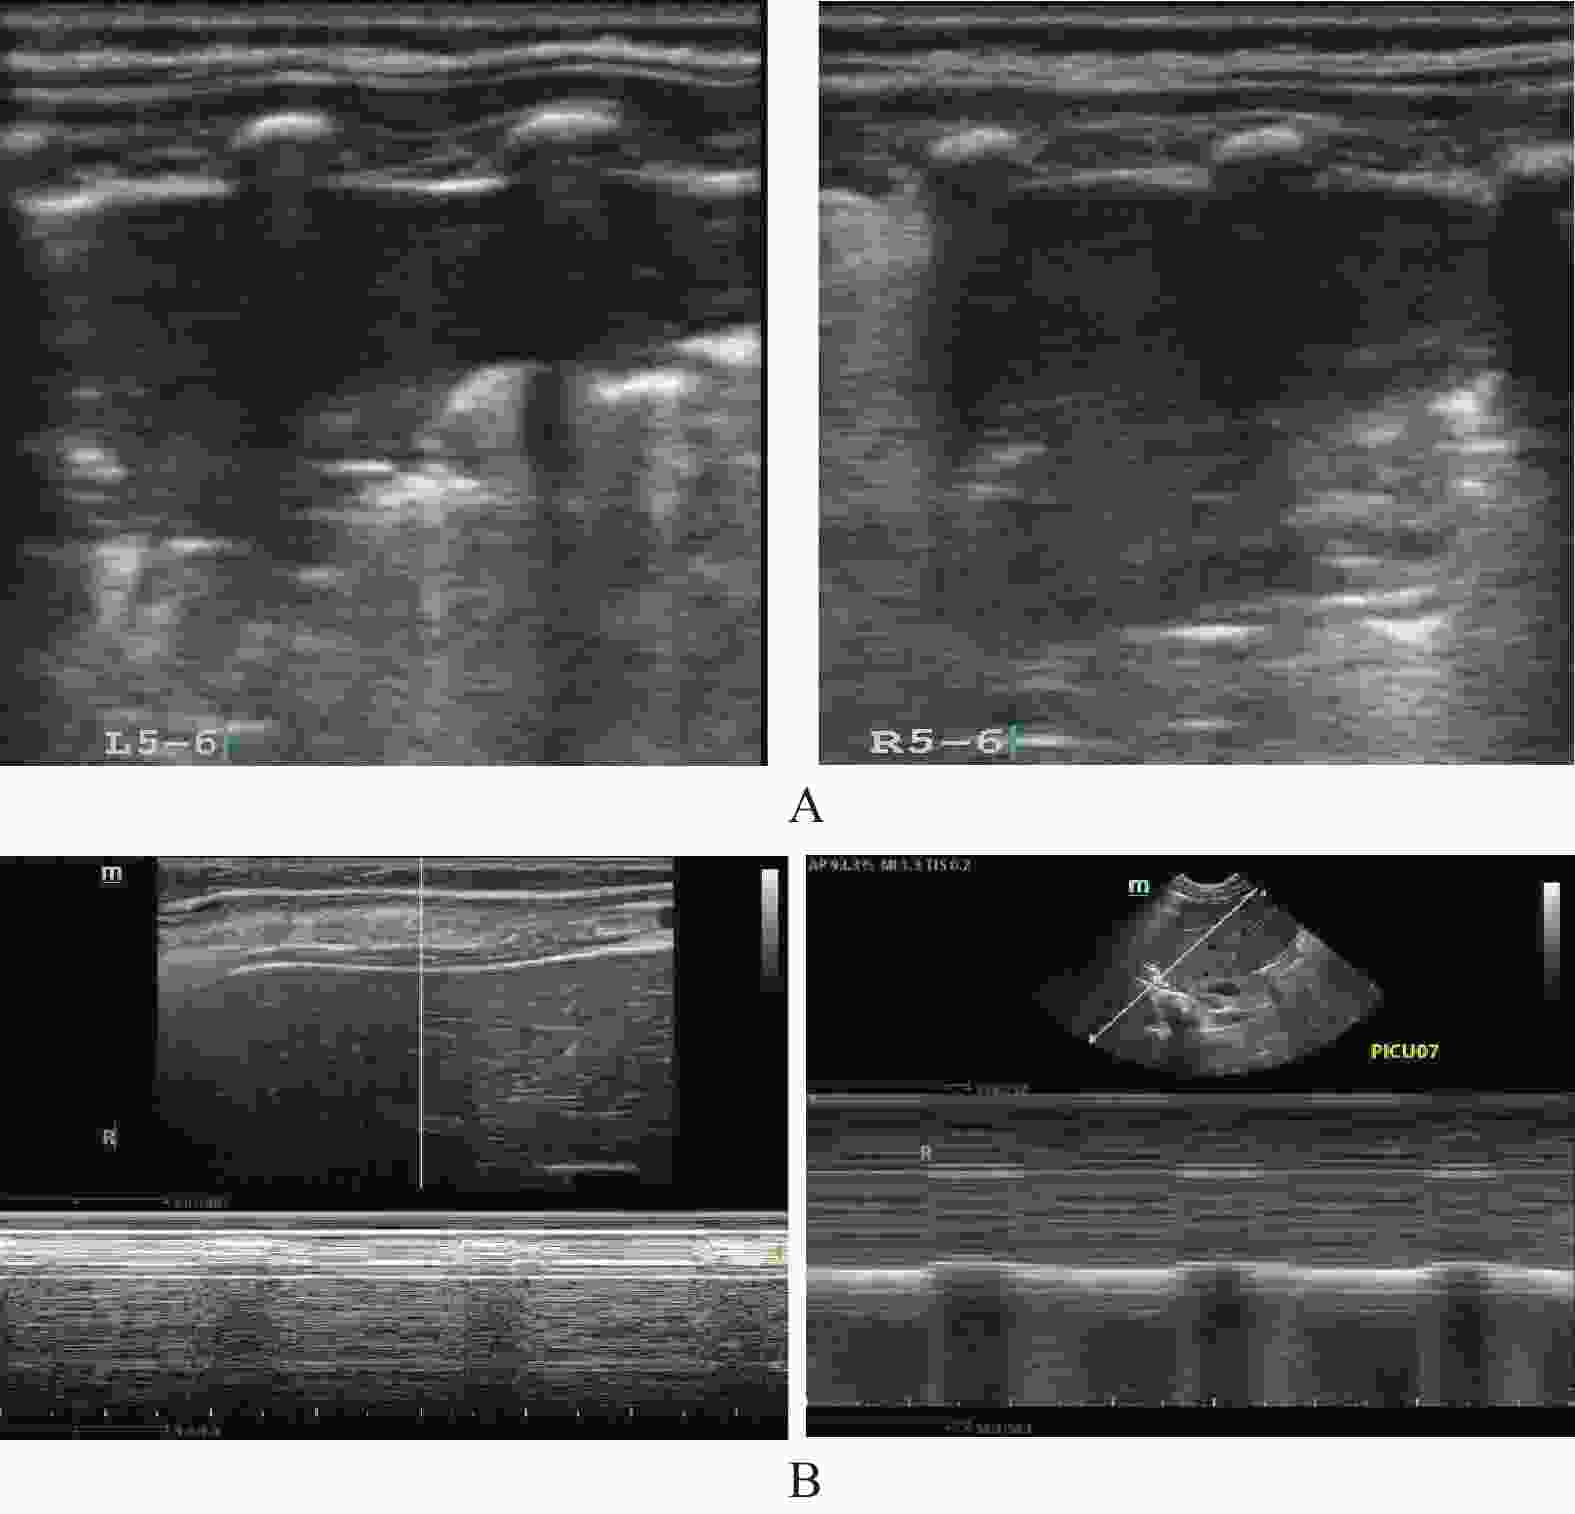

目的 探究肺部超声评分(LUS)、膈肌超声联合常规指标预测小儿重症肺炎(SP)并发急性呼吸窘迫综合征(ARDS)的价值。 方法 选取2022年8月至2023年8月昆明市儿童医院SP患儿160例,均行肺部超声、膈肌超声检查获取LUS、膈肌超声参数[膈肌移动度(DM)、膈肌厚度变化率(TF)],根据SP患儿住院期间是否并发ARDS分为ARDS组67例和非ARDS组93例,比较两组入院时一般资料、血清炎症因子水平、LUS、膈肌超声参数,分析SP患儿并发ARDS的影响因素,并分析LUS、膈肌超声参数预测SP患儿并发ARDS的价值。 结果 SP患儿住院期间ARDS发生率为41.88%(67/160);ARDS组入院时APS、APACHEⅡ评分、血清C反应蛋白(CRP)、白介素-6(IL-6)、高迁移率族蛋白B1(HMGB1)水平、LUS、DM高于非ARDS组,TF低于非ARDS组(P < 0.05);入院时APS、APACHEⅡ评分及血清CRP、IL-6、HMGB1水平、LUS、DM、TF均为SP患儿并发ARDS的影响因素(P < 0.05);LUS、DM、TF预测ARDS的曲线下面积(AUC)分别为0.718、0.742、0.720;常规预测方案(入院时APS、APACHEⅡ评分及血清CRP、IL-6、HMGB1水平联合)的AUC为0.852,新预测方案(常规预测方案基础上联合LUS、DM、TF)的AUC为0.930,新预测方案的AUC明显大于常规预测方案的AUC(P < 0.05)。 结论 LUS、膈肌超声参数DM、TF与SP患儿并发ARDS显著相关,联合常规指标可为临床预测SP患儿并发ARDS提供可靠依据。 Abstract:Objective To explore the value of lung ultrasound score (LUS) and diaphragm ultrasound combined with routine indicators in predicting the occurrence of acute respiratory distress syndrome (ARDS) in children with severe pneumonia (SP). Methods A total of 160 patients with SP were selected from Kunming Children’s Hospital from August 2022 to August 2023, all of whom underwent lung ultrasound and diaphragm ultrasound examination to obtain LUS and diaphragm ultrasound parameters [diaphragm mobility (DM), diaphragm thickness change rate (TF)]. The patients with SP were divided into ARDS group and non-ARDS group according to whether they were complicated with ARDS during hospitalization. The general data, serum inflammatory factor levels, LUS and diaphragm ultrasound parameters were compared between the two groups at admission, and the influencing factors of ARDS in children with SP were analyzed, and the value of LUS and diaphragm ultrasound parameters in predicting ARDS in children with SP was analyzed. Results The incidence of ARDS in SP patients was 41.88% (67/160). APS, APACHEⅡ scores, serum C-reactive protein (CRP), interleukin-6 (IL-6), high mobility group protein B1 (HMGB1) levels, LUS and DM in ARDS group were higher than those in non-ARDS group, TF were lower than those in non-ARDS group (P < 0.05). APS, APACHEⅡ scores, serum CRP, IL-6, HMGB1 levels, LUS, DM, TF were the influencing factors of ARDS in SP children at admission (P < 0.05). The area under the curve (AUC) of LUS, DM and TF predicted ARDS were 0.718, 0.742 and 0.720, respectively. The AUC of the conventional prediction scheme (APS, APACHEⅡ score combined with serum CRP, IL-6 and HMGB1 levels at admission) was 0.852, while that of the new prediction scheme (combined with LUS, DM and TF based on the conventional prediction scheme) was 0.930. The AUC of the new prediction scheme was significantly higher than that of the conventional prediction scheme (P < 0.05). Conclusion LUS, DM, TF, and SP parameters of the diaphragm are significantly correlated with ARDS in children with SP, and the combination of routine indicators can provide reliable evidence for clinical prediction of ARDS in children with SP. -

组别 n LUS(分) DM(cm) TF(%) ARDS组 67 20.15±3.26 1.41±0.34 37.24±3.65 非ARDS组 93 17.48±2.51 1.12±0.28 41.08±4.13 t 5.852 5.905 6.087 P <0.001* <0.001* <0.001* *P < 0.05。 表 3 SP患儿并发ARDS的影响因素分析

变量 β SE Wald OR 95%CI P 下限 上限 APS 0.275 0.097 8.024 1.316 1.185 1.462 <0.001* APACHEⅡ 0.207 0.075 7.618 1.230 1.129 1.340 <0.001* CRP 0.251 0.089 7.925 1.285 1.164 1.418 <0.001* IL-6 0.301 0.098 9.409 1.351 1.201 1.519 <0.001* HMGB1 0.233 0.084 7.676 1.262 1.150 1.385 <0.001* LUS 0.380 0.112 11.487 1.462 1.302 1.641 <0.001* DM 0.318 0.096 10.946 1.374 1.228 1.537 <0.001* TF −0.118 0.041 8.243 0.889 0.813 0.972 <0.001* *P < 0.05。 表 4 LUS、膈肌超声参数预测SP患儿并发ARDS的价值

Table 4. Value of LUS and diaphragm ultrasound parameters in predicting ARDS in children with SP

指标 AUC 95%CI 截断值 敏感度(%) 特异度(%) LUS 0.718 0.641~0.786 19.02分 68.66 69.89 DM 0.742 0.668~0.809 1.33 cm 73.13 75.27 TF 0.720 0.644~0.788 38.50% 64.18 73.12 表 5 不同预测方案的预测SP患儿并发ARDS的价值比较